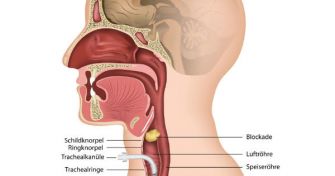

Luftröhrenschnitt: Therapie in Extremsituationen

Zum System der Atmungsorgane gehören die Nase, der Mund und der Rachen, der Kehlkopf, die Luftröhre, die Bronchien und die Alveolen der Lungen, wo der Gasaustausch stattfindet. In speziellen Situationen ist ein operativ geschaffener Zugang zur Luftröhre, einem Luftröhrenschnitt, im Fachjargon Tracheotomie bezeichnet, notwendig, um die ...